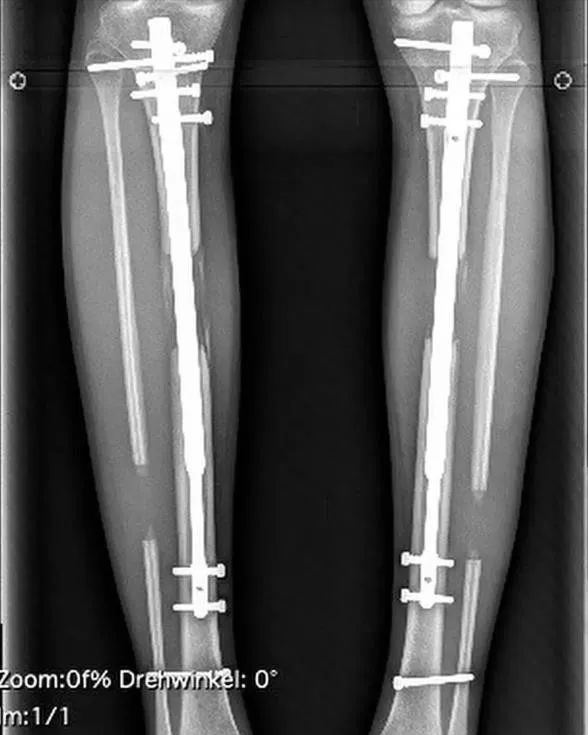

这位金发美女在24岁时,在腿骨中植入了可调节的伸缩杆,逐渐伸长她的腿部。

她描述了这项手术的可怕之处:“胫骨被干净地断开,小腿肌肉被分开,然后在每个情况下使用一个伸缩杆。你可以独立地通过一只手握住膝盖,另一只手向内拧脚,直到它发出咔哒声,来伸展你的小腿。每天每侧点击十次,可以多增加0.5毫米 [0.02英寸]。”